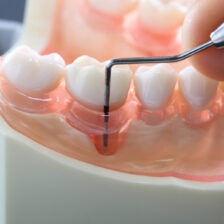

根管治療の成功率を上げるためには、知識や経験はもちろんですが、精密な治療に対応するための設備や器具も不可欠です。

当院では、歯科用顕微鏡(マイクロスコープ)や歯科用CBCT、ラバーダム、ニッケルチタンファイルなど、患者さんにより良い治療を提供するための設備・器具を揃えております。